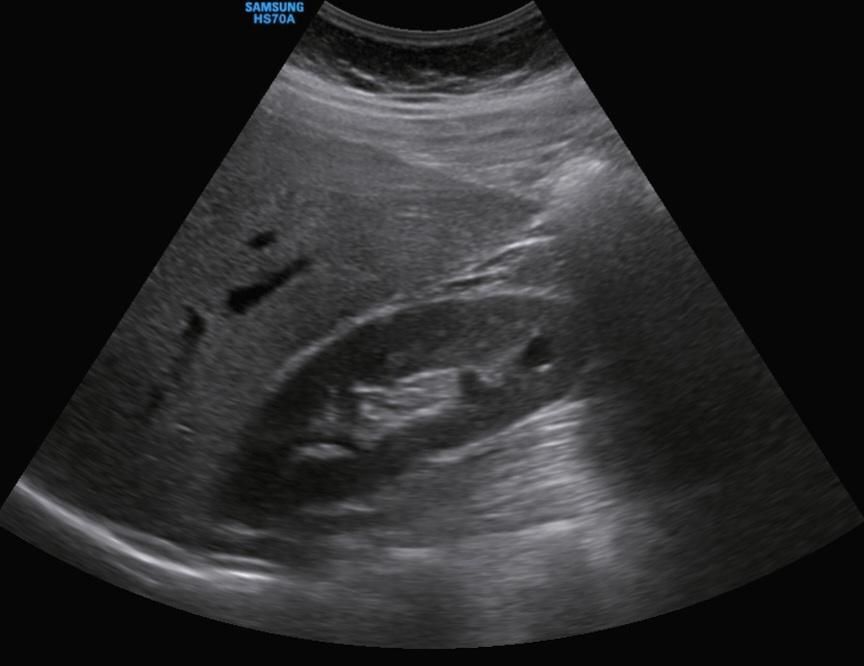

신장 낭종 복부초음파 봐주실분... 안에 하얀선?

그리고 이번년도에 복부초음파에서 1.05cm 발견했어요.

복부초음파 사진을 올립니다.

특히 안에 완전 검은색이 아니라 흰색선? 이 있어요..ㅠㅠ여자에요

• 1번 째 사진